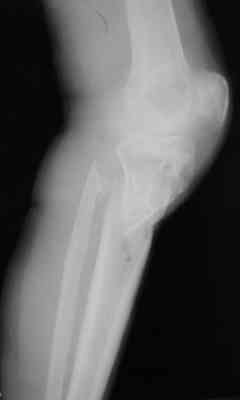

Р-граммы за март и апрель